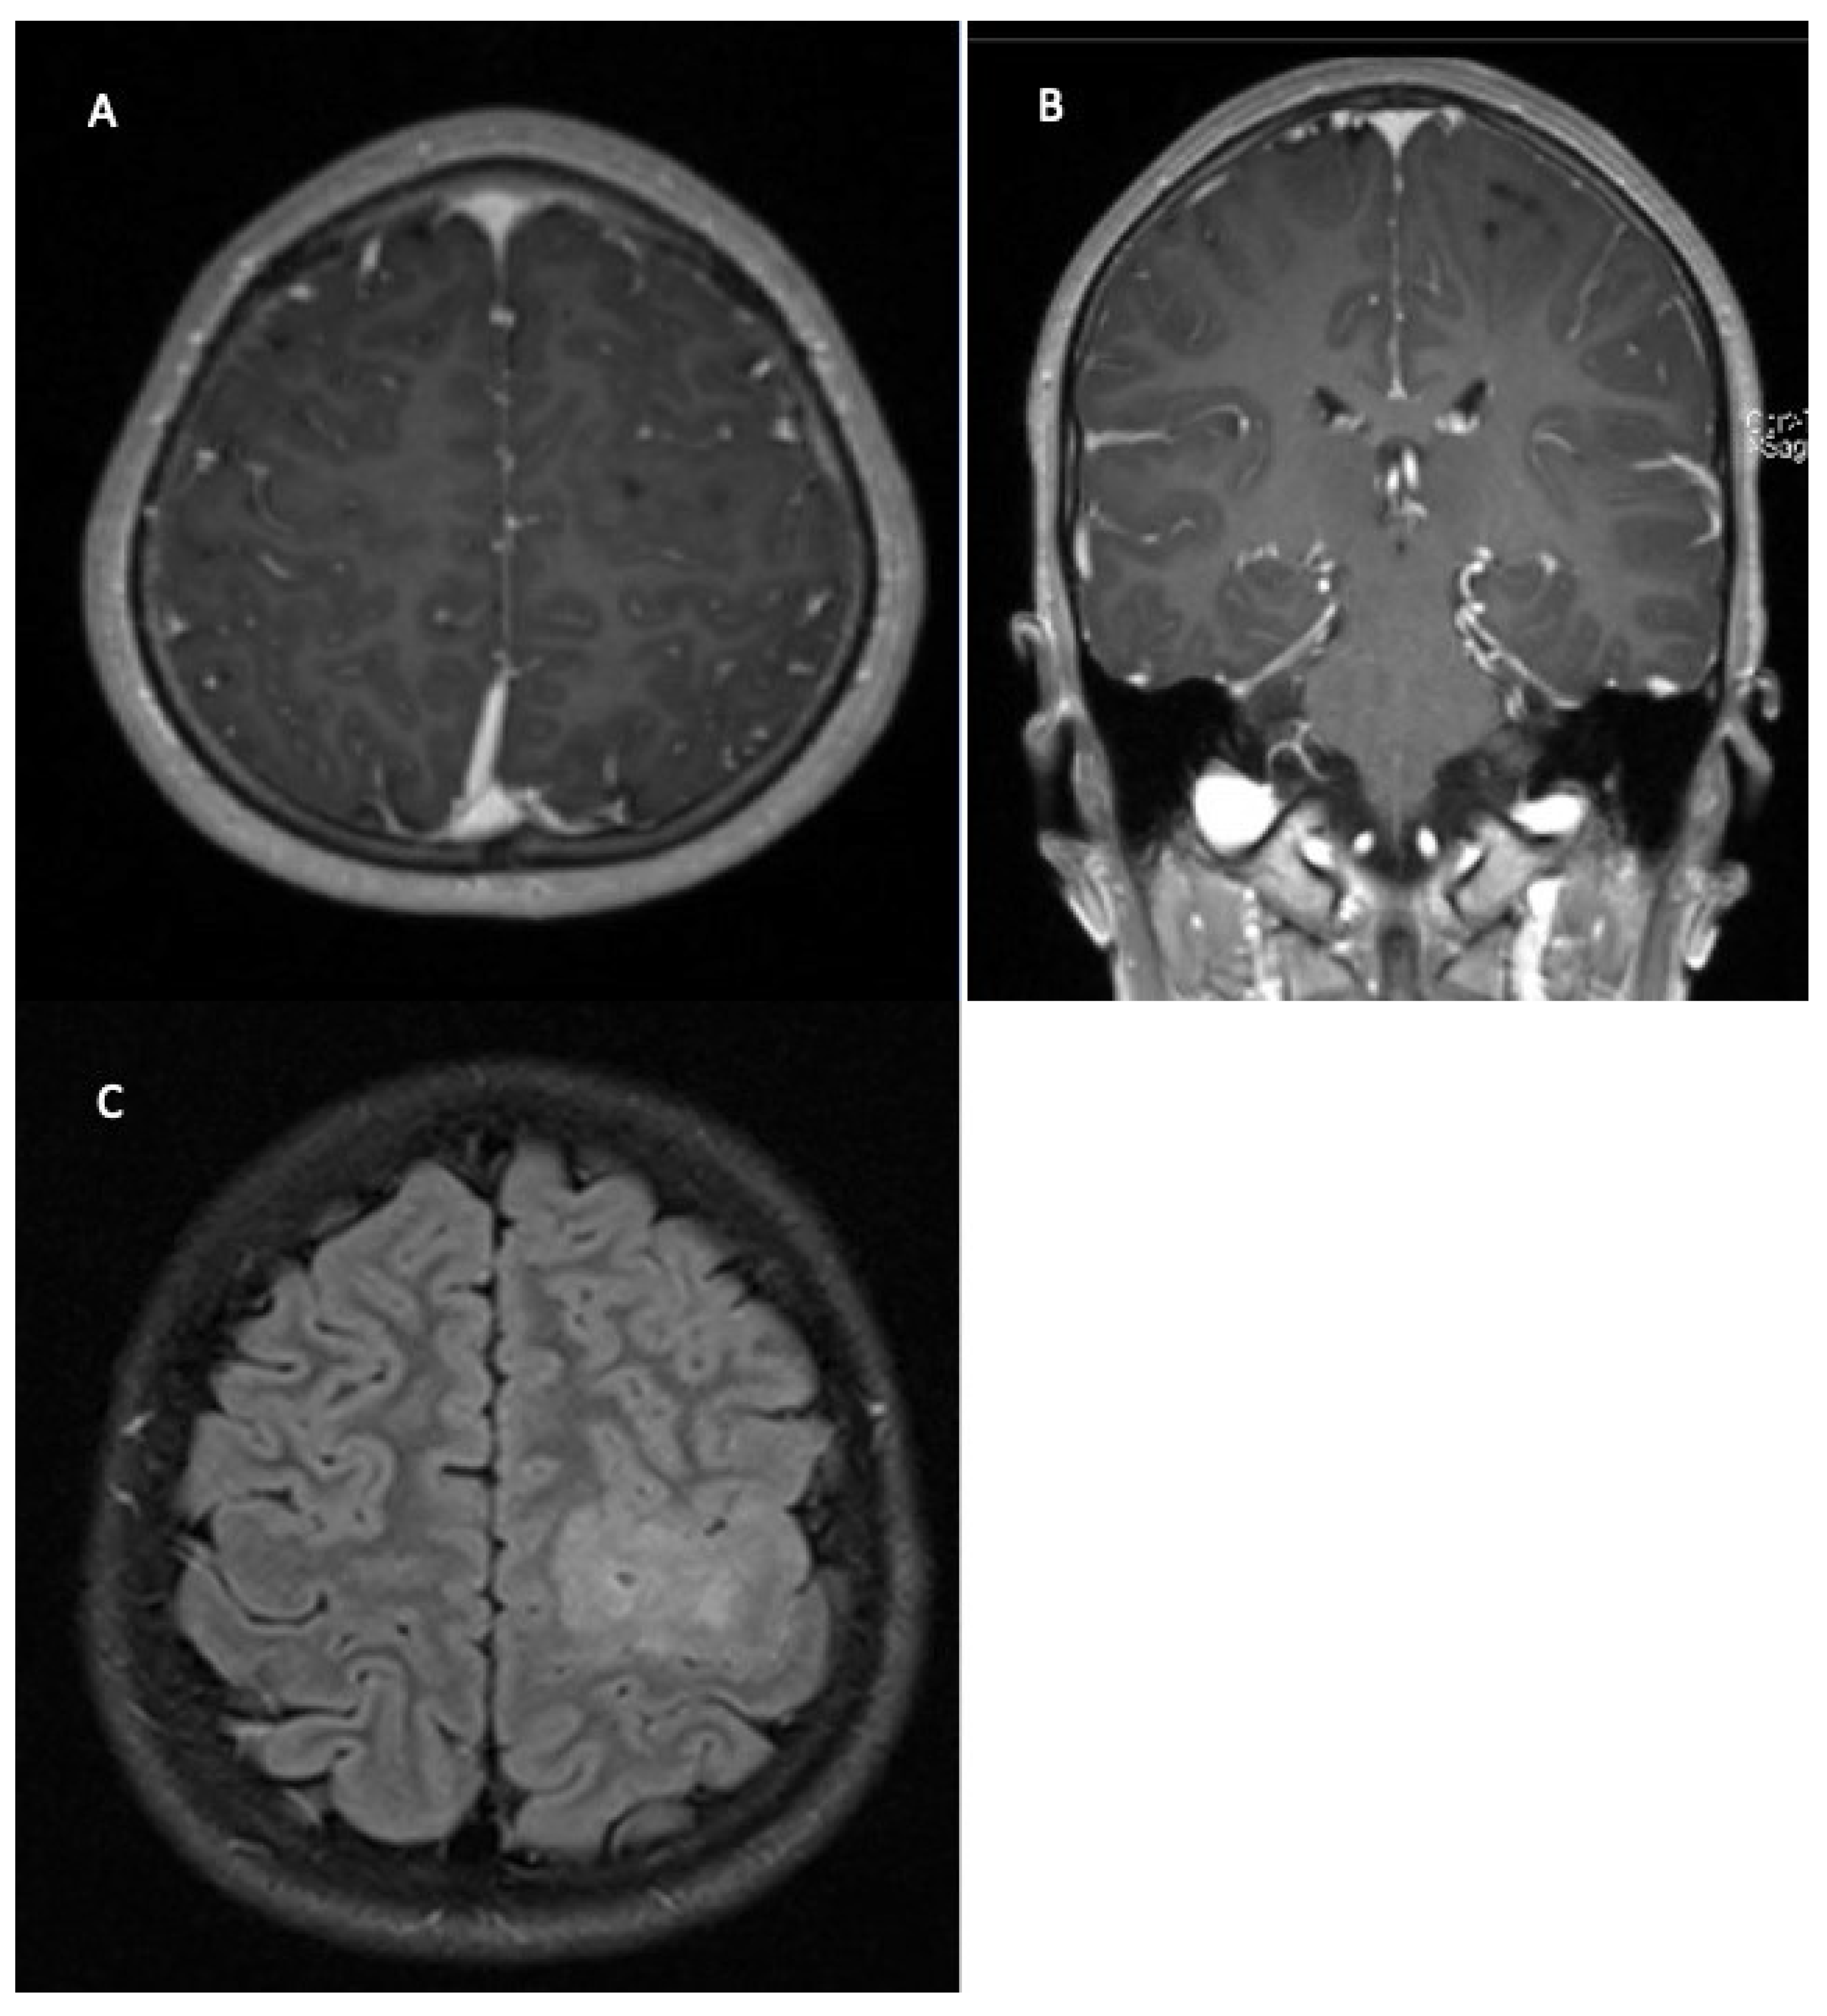

2. Clinical Assessment/Symptoms

3. Diagnostics